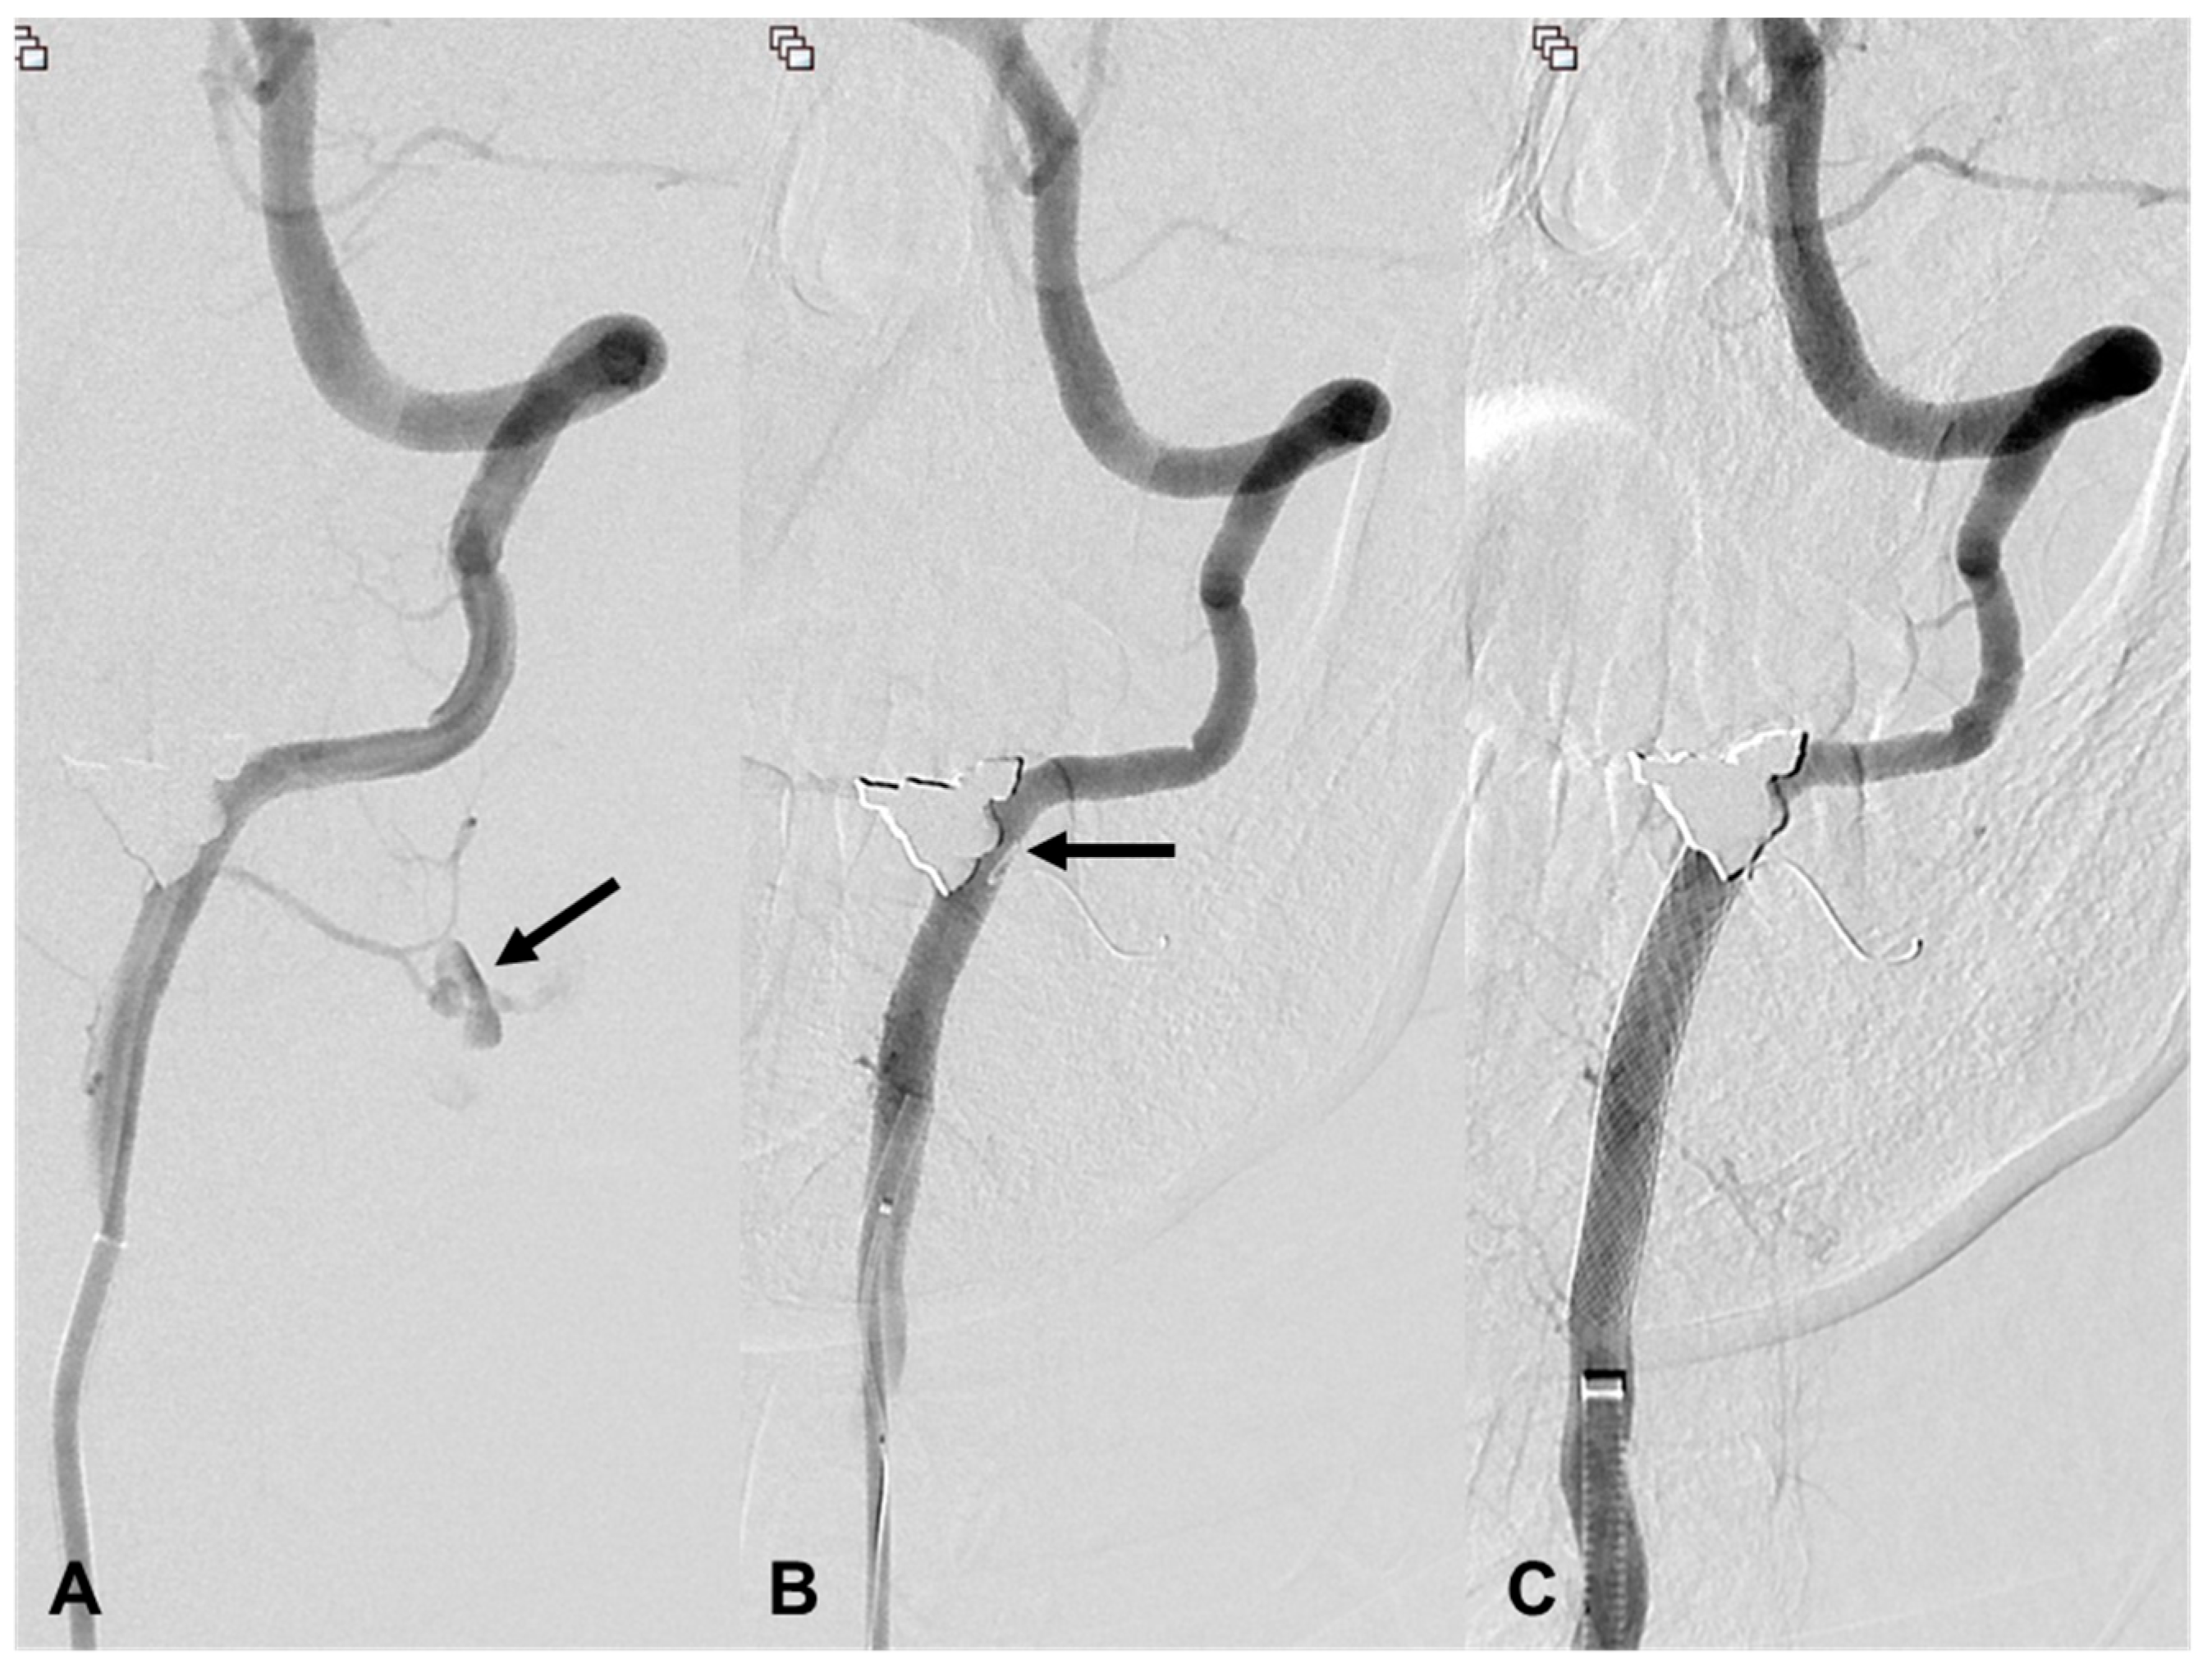

3.4. Carotid Artery Injury

| 12 | 47/M | Stab | Arrest | R CCA-IJV fistula | EV, R distal CCA | cStent | Death 12 h d/t hypovolemic shock |

| 15 | 34/F | Stab | Bleeding | EV, R ICA | EV, R cervical ICA | cStent | Stable 45 d F/U |

| 16 | 32/M | Iatrogenic | Massive bleeding during surgery | NA | EV, R proximal CCA | cStent | Stable 2344 d F/U |

| 18 | 58/M | Iatrogenic | Oral bleeding | NA | EV, L cervical ICA | cStent | Death 354 d d/t pneumonia |